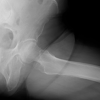

Case 3 (male, 47 years) has had more extensive osteolysis affecting the ischium and pubis (type IIIa) with severe metallosis and sander marks on the head’s surface. Metal wear was seen in the histologic samples. Extensive bone grafting of the defects in the ischium (12 cm3) and pubis (8 cm3) was necessary. The stem was clinically loose at surgery and was revised using a solution stem (DePuy) through an extended trochanteric osteotomy, plus a trochanteric grip plate due to refixation of periprosthetic trochanteric fracture (Trofix®, Zimmer, Fig. 1b). The primary surgery was 10.0 years ago (01/02–12/11). Retrieved implants demonstrated significant volumetric wear of the liner (up to 2.84 cm3) with either partial or complete loss of the TiN coating and volumetric wear of the TiALV-heads. In all three cases, the TiN coating was delaminated to varying but significant extents. No backside wear or liner damage was noted. Measurements were done by three independent blinded assessors and averaged. An electronic digital caliper (digiMax, Swiss Precision Instruments, Inc.,) was used. The damaged femoral head coating ranged 0.5 cm2 (elderly patient) to 5.75 cm2 (two younger patients, Fig. 1). The two younger patients also had a defect of the TiALV head itself. All defects were palpable. The head diameter was reduced by 0.19 mm (32 mm head) and 0.18 mm (28 mm head). Histologically, a range of mild to severe metallosis was found in three cases in addition to wear-induced synovitis [4,5]. All patients suffered from mainly load depending hip pain without neurological symptoms.